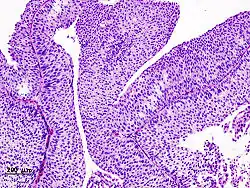

Transitional cell carcinoma, being low-grade to the left, and high-grade to the right. H&E stain -

Papillary transitional cell carcinoma, low grade -